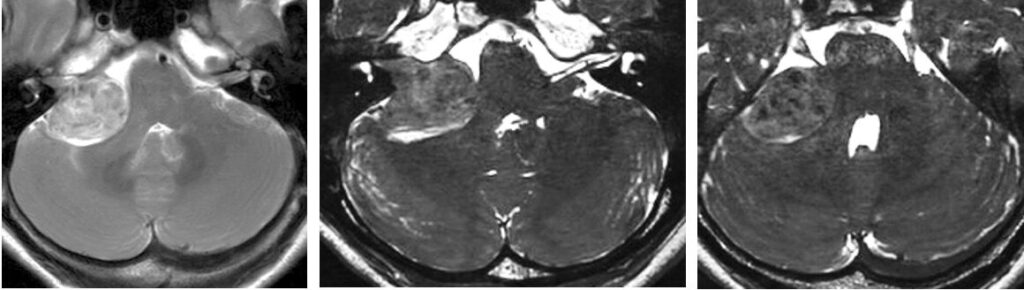

- 脳動静脈奇形・脳幹部血管腫